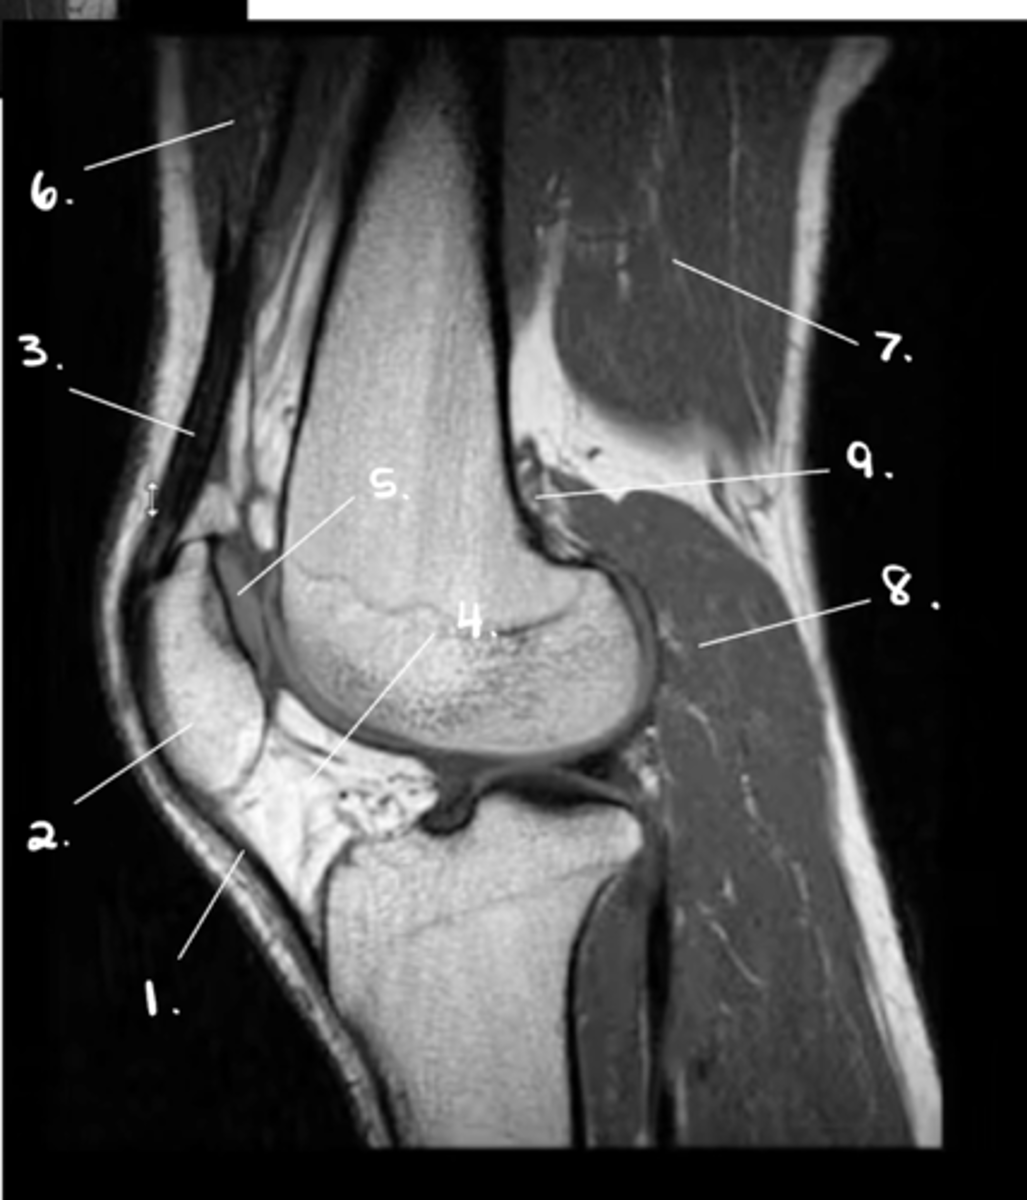

1. Patellar tendon

2. Patella

3. Quadriceps tendon

4. Hoffa's fat pad

5. Retro-surface cartilage of patella

6. Quadriceps

7. Hamstrings

8. Gastroc.

9. Poplitus

Label 1-9.